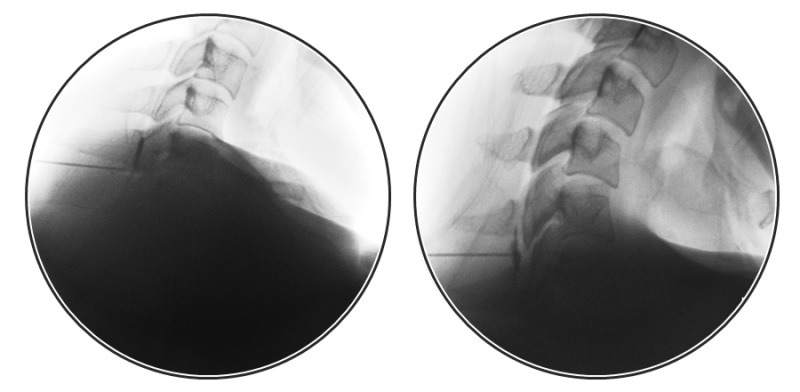

씨아이테라피는 경추와 요추의 추간판 탈출증 치료에 탁월한 결과를 보여온 비수술적 척추치료입니다. 척추관협착증이나 추간판 탈출증의 급성 염증기에 척수와 그로부터 나오는 신경을 둘러싼 공간인 경막외강으로 주사하여 신경 주변의 염증을 정화하고 진정시키는 시술입니다. 급성기. 이동형 엑스레이라고 할 수 있는 특수 영상기기인 C-arm을 관찰하면서 원하는 신경 염증 부위에 약물을 직접 주입한다. 흔히 단순 주사치료라고 생각되는 시술도 통증 부위와 증상에 따라 40가지 이상의 기법으로 시술이 가능하기 때문에 경험이 풍부한 전문의의 시술이 무엇보다 중요합니다. 분당서울대병원 등 대학병원에서는 척추치료와 같은 기본적인 치료가 가장 효과적인 치료방법이지만 CI치료는 숙련된 전문의가 많지 않고 기술도 다양해 종합병원에서는 거의 이뤄지지 않고 있다. 꼬끄통증클리닉은 정확한 질병분류를 통해 치료계획을 수립합니다. CI치료만으로는 해결되지 않는 관절, 근육, 인대의 척추치료를 위해 만성경추추간판과 같은 추간판의 안정기에 효과적인 “SI치료(초음파유도주사요법)”와 추간판 탈출증, 수행됩니다.